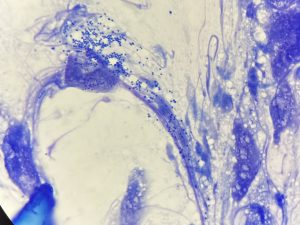

下の写真は犬歯が折れてしまった猫ちゃんです。

レントゲン検査では根尖病変を疑う所見はありませんでした。

破折した直後で神経も止血されており、生活歯髄切断を行いました。

・露髄、止血の確認